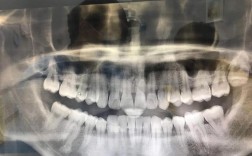

| 全景片(曲面断层片) | 观察全口牙齿的发育、萌出情况,牙根形态、长度,牙槽骨高度,以及是否存在埋伏牙、多生牙、囊肿等 | 常规初诊筛查,了解牙齿整体排列和牙根状态 |